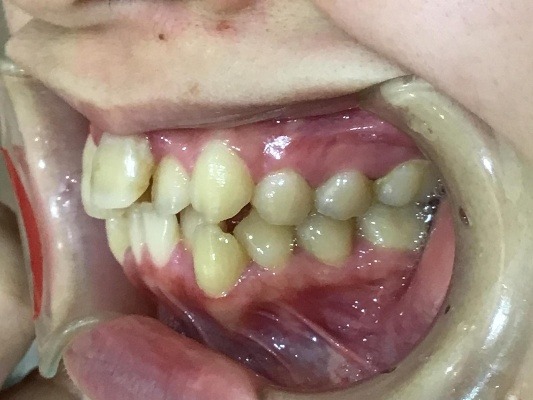

右横

左横

| 治療詳細 | 叢生や交叉咬合を整えるために、歯の表面にアタッチメント(白い突起)をつけ、IPR(歯と歯の間を削る)を行いました。 また、顎間ゴムと呼ばれる引っ掛けるゴムの補助装置も用いて治療を行いました。 抜歯を1本して治療を行いました。該当部分は義歯を使用しています。 |

| 主訴 | 歯のがたつき 一部分だけかみ合わせが反対 |